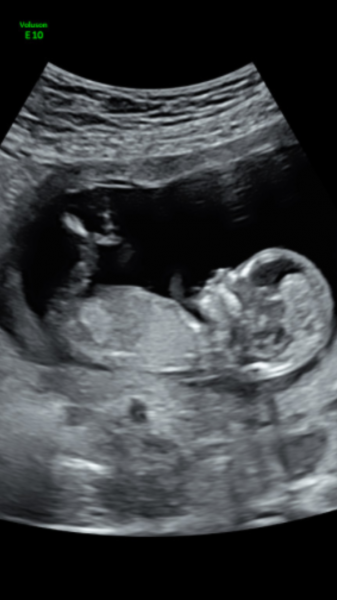

Vill ngn gissa den är i vecka 19(18+6 ) beräkna 18/2-18